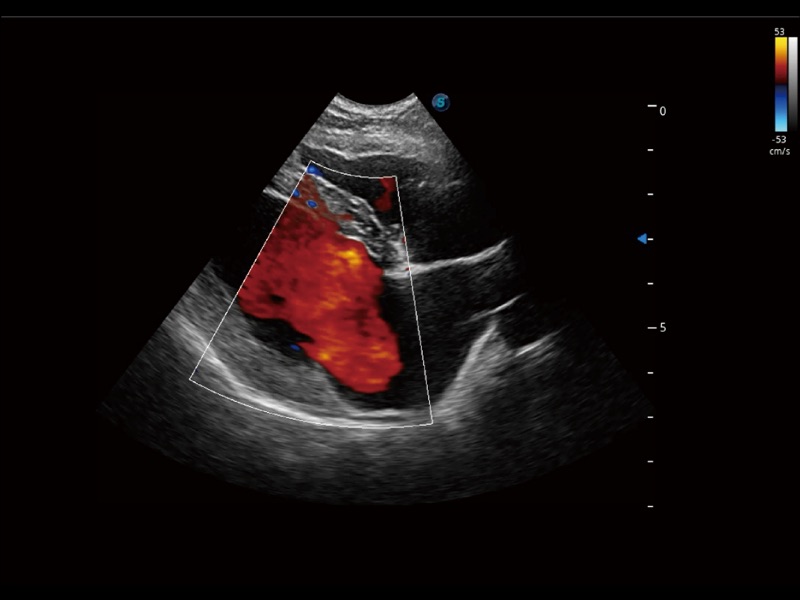

采用红、橙、黄、绿、青、蓝、紫这七种肉眼最为敏感的色彩,直观地显示组织内血流灌注的时间先后信息,更精准捕捉血流灌注走行细节。

通过创新的 Matrix E自适应滤波器和超长时间域算法,极大提升超低速微细血流的检出能力,同时更精准地滤除软组织和噪声信号,为兽用医生提供以往无法通过常规血流获得的疾病诊断信息。

实时用颜色表示心肌组织运动,观察和定量组织的运动情况,对快速检测与评估心肌的灌注和活性、电传导及心肌收缩和舒张功能等均能提供重要的诊断信息。